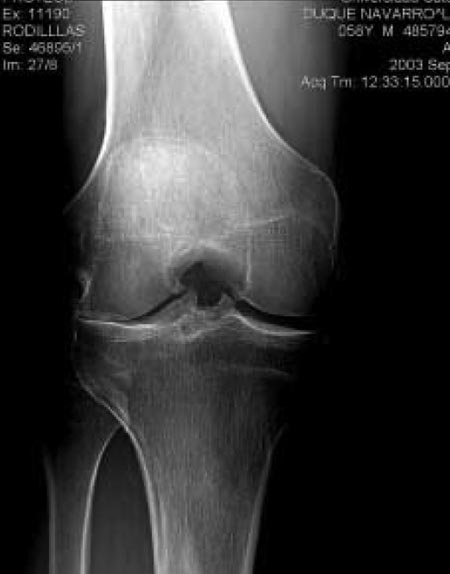

Se pudo observar que la proyección de Rosenberg en comparación con la proyección AP tiene mayor capacidad de detectar la disminución del espacio articular cuanto mayor es éste (más espacio remanente), es decir la proyección de Rosenberg, a diferencia de la proyección AP convencional es capaz de detectar estadios de artrosis incipiente (Gráfico 1). A medida que la enfermedad progresa y existe una disminución considerable en la altura del espacio articular, ambas proyecciones tienen un rendimiento similar. (Fig. 2A y 2B).

Figura 2A: Proyección radiográfica AP convencional de un paciente con síntomas de gonartrosis. Los espacios articulares se ven conservados.

Figura 2B: Proyección de Rosenberg del mismo paciente, una importante disminución del espacio tibiofemoral lateral.